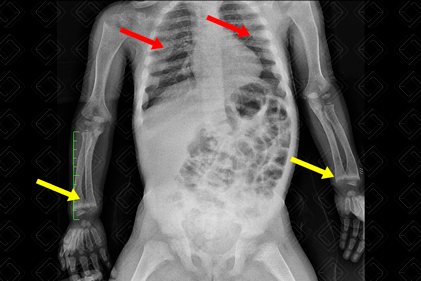

Radiografia de tórax evidenciando presença de rosário raquítico ( setas vermelhas) e aspecto franjeado nas metáfises distais dos rádios e ulnas, bilateralmente (setas amarelas). Figura 3 - Créditos: Dra Elazir Mota - Rio de Janeiro/RJ

Descrição da lesão: Radiografia dos membros superiores e mãos (figuras 1 e 2). Alargamento das fendas epifisárias e metafisárias da ulna e rádio, bilateralmente. As metáfises apresentam aspecto franjeado. Osteopenia difusa. Estes achados radiológicos são típicos do raquitismo.

Figura 3: Radiografia de tórax evidenciando presença de rosário raquítico (setas vermelhas) e aspecto franjeado nas metáfises distais dos rádios e ulnas, bilateralmente (setas amarelas).